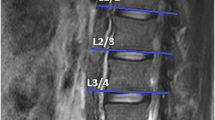

In this retrospective study, texture analysis (TA) was performed on postprocessed axial T2 weighted (w) MR images at level L3/4 using dedicated software (MaZda) in 62 patients with LSS. Associations in fatty infiltration between qualitative Goutallier and quantitative TA findings with two clinical outcome measures, Spinal stenosis measure (SSM) score and walking distance, at baseline and regarding change over time were assessed using machine learning algorithms and multiple logistic regression models.